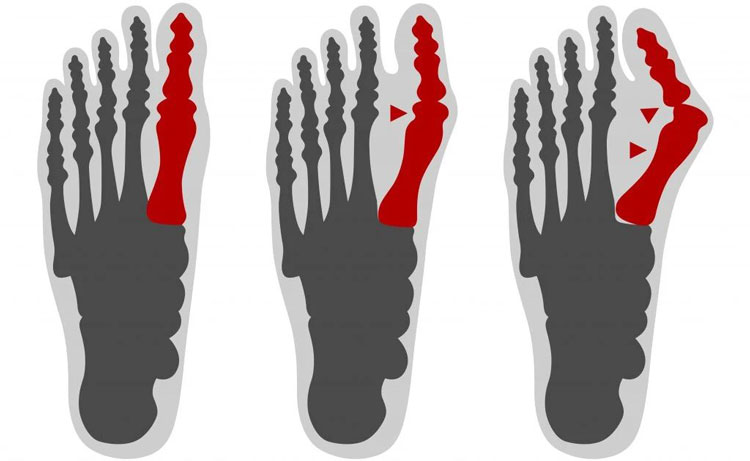

Fase dell'alluce valgo in cui la chirurgia è indispensabile

Fase dell'alluce valgo in cui la chirurgia è indispensabile